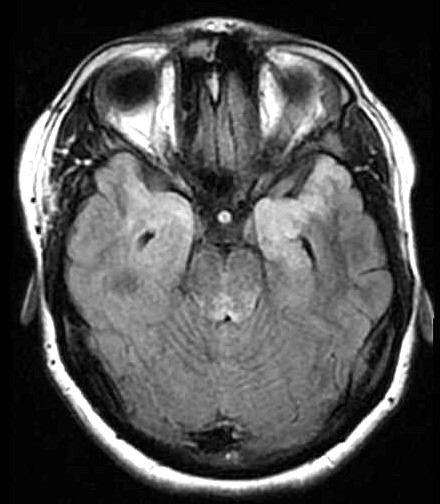

| Fem. 17a. |

| Nódulo sólido homogêneo preenchendo o III ventrículo, com limites precisos, com hipossinal em T1 e hipersinal em T2 e FLAIR, que se impregna por contraste paramagnético. Lesão menor implantada no assoalho do IV ventrículo provavelmente representa disseminação por via liquórica. |

| CORTES AXIAIS, T1 COM CONTRASTE | ||

| F. 17a. Tumor teratóide rabdóide atípico de III ventrículo. RM | HE | VIM, GFAP | HHF35, desmina, 1A4 | AE1AE3, EMA |